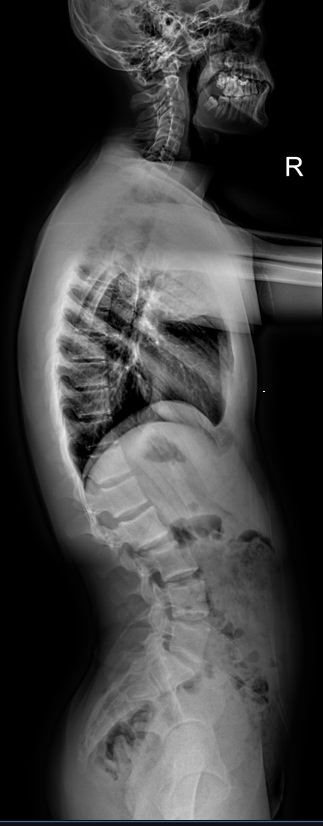

Назад Рентген позвоночника на кифосколиоз в прямой и боковой проекциях

При появлении признаков кифосколиоза или подозрении на него врач в качестве первичного обследования обычно назначает рентген. При этом рекомендован снимок всего позвоночного столба: как для выявления различных аномалий развития позвонков, так и для определения углов отклонения и, соответственно, степени заболевания. Для этого делают несколько обычных прицельных снимков и соединяют их в один с помощью компьютера. Несмотря на большую, казалось бы, дозу облучения, волноваться не стоит. Современное цифровое рентгеновское оборудование излучает настолько маленькую дозу, что даже при серии снимков трудно набрать допустимое для человеческого организма количество облучения.

Врач-рентгенолог  высчитывает углы возникшей деформации. Для определения угла кифоза на боковой рентгенограмме вычерчиваются линии, соединяющие нейтральные, то есть не измененные позвонки, с тем, что находится на самой вершине. Угол между ними и будет искомым. Угол сколиоза определяют по снимку в прямой проекции.

Для диагностики кифосколиоза необходимы 6 снимков:

• Шейного, грудного и пояснично-крестцового отделов в прямой проекции;

• Те же самые отделы в боковой проекции в состоянии максимального разгибания.